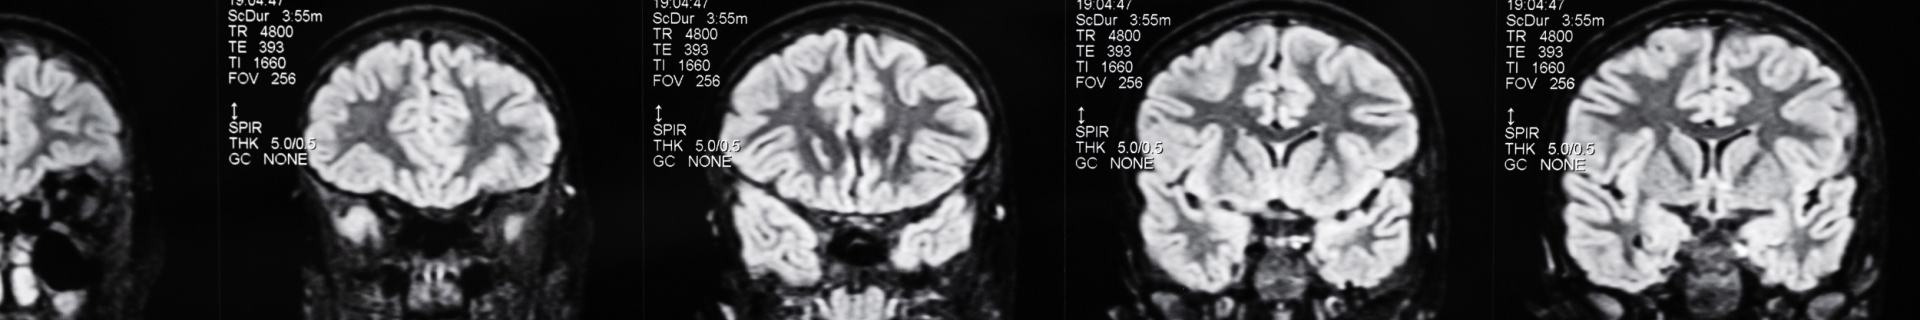

Pour le paléoanthropologue spécialiste de l’évolution humaine Jean-Jacques Hublin, « la grande affaire de notre évolution durant les derniers 300.000 ans est bien notre cerveau » : il a fallu 2,5 millions d'années pour passer d'un cerveau gros comme celui d'un chimpanzé au cerveau actuel de l’homme, caractérisé par un accroissement cérébral très supérieur à celui observé chez les grands singes. Mais comment le cerveau de l'homme a-t-il pu devenir le plus perfectionné ?